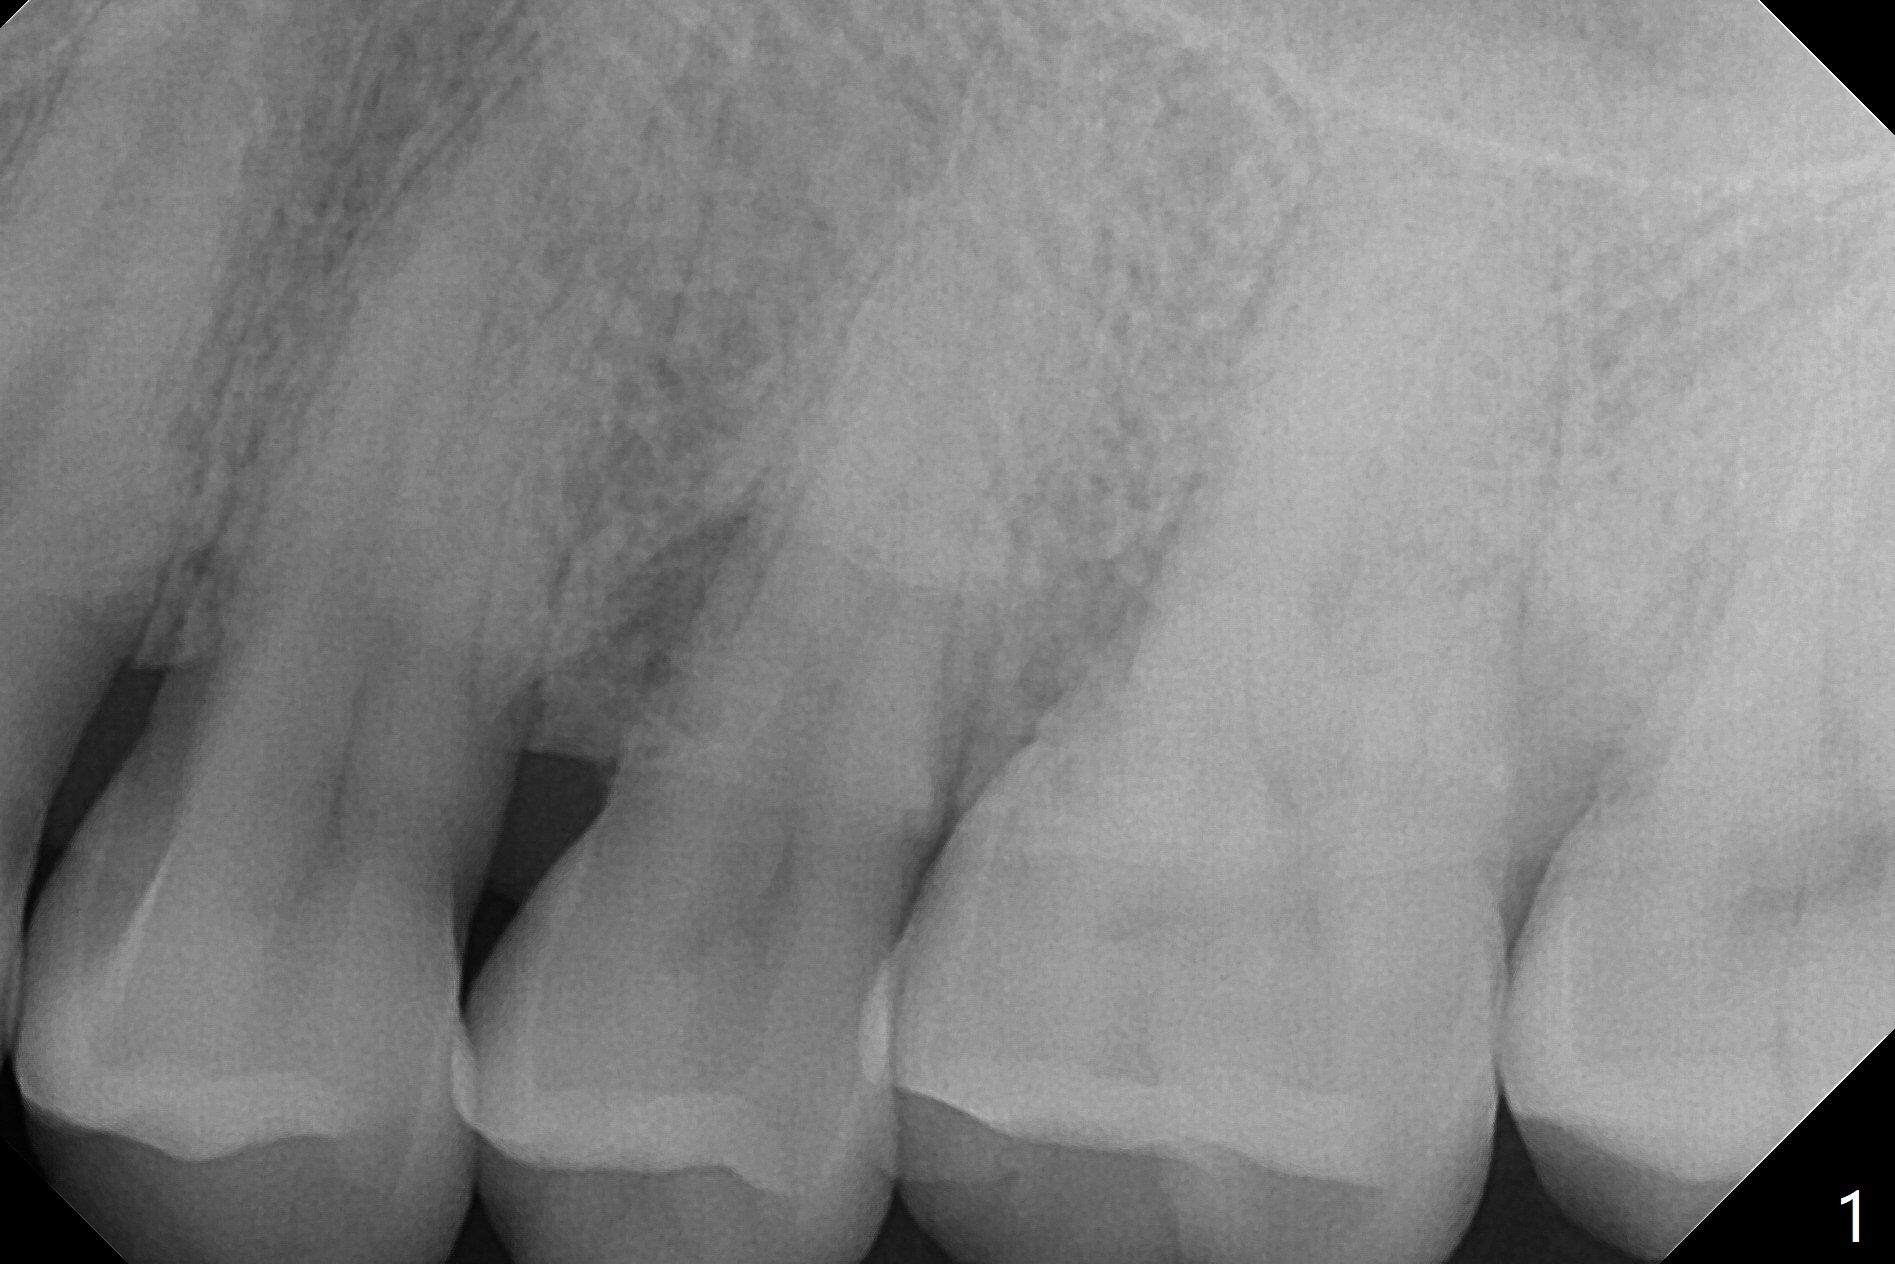

A 44-year-old man presented to clinic with pain of the upper left quadrant (Fig.1), but the affected tooth was not determined until 5 months later (Fig.3,4). Retrospectively the minor crack is visible earlier (Fig.2 arrowheads). It appears that the remaining bone (sinus floor) is limited (Fig.5). Magic Sinus lift or Magic Expanders will be used for sinus lift. Prepare 2-3 pieces of PRF membranes: one or two for sinus lift; the third one to close the socket if primary stability is <30 Ncm.